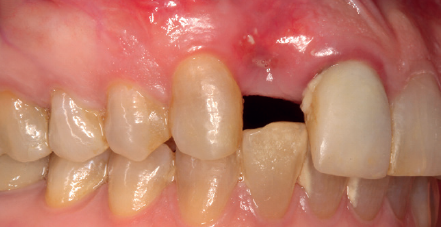

Se presenta el caso de una mujer de 36 años que acude a la consulta demandando solución para un implante situado en la posición 1.2. Este implante ha llevado una rehabilitación con una corona durante un corto período de tiempo en el que se produjo una mucositis importante y una pérdida del grosor del tejido gingival, por lo que la corona fue retirada.

La paciente presenta un provisional removible y el tejido blando circundante a la zona de la emergencia inicial de la prótesis implantosoportada se encuentra en malas condiciones, con una pérdida de grosor importante y los restos de una fístula de tejido blando (Figuras 1-4).